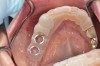

(1. AND 2.) Removable appliance.

Figure 1

Figure 2